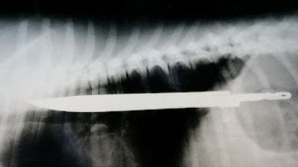

Taguri: a înghițit cuțite Un indian a ajuns la spital după ce A ÎNGHIȚIT 40 de cuțite 1 ABCDEFGHIJKLMNOPQRSTUVWXYZ IMPORTANTE ALTELE